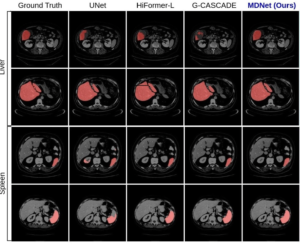

MDNet: Multi-Decoder Network for Abdominal CT Organs Segmentation

Authors: Debesh Jha, Nikhil Tomar, Koushik Biswas, Gorkem Durak, Matthew Antalek, Zheyuan Zhang, Bin Wang, Md Mostafijur Rahman, Hongyi Pan, Alpay Medetalibeyoglu, Abhijit Das, Yury Velichko, Daniela P. Ladner, Amir A. Borhani, Ulas Bagci

IEEE ICASSP 2025

Publication Year: 2025